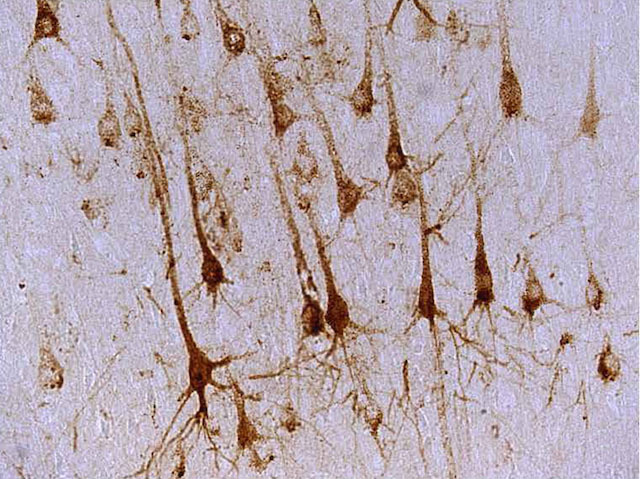

Wintery Neurons

For some people this picture resembling an upside-down watercolour of leafless trees, may bring thoughts of bleak mid-winter, but for the scientists whose hard work the image represents, the thoughts are likely to be more joyful and triumphant. The trees are in fact neurons in a section of brain from a dog that has been successfully treated with gene therapy. Brown staining of the cells shows the presence of the gene's product: an enzyme called TPP1. Kids with mutations in the TPP1 gene develop a rare but devastating neurodegenerative condition called Batten disease, which is characterised by seizures and the gradual loss of vision, speech, cognitive ability and mobility. Death before age ten is common. Encouragingly, in dogs with a naturally occurring version of the disease just one dose of TPP1 gene therapy resulted in the animals living longer with noticeable improvements in their cognitive ability and quality of life.